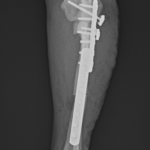

2歳の柴犬ちゃんが、生まれてすぐに痛めた肘に徐々に痛みが出てきたとのことで、主治医から診察と必要があれば手術をして欲しいと連絡がありました。CTでは橈骨頭が外側に脱臼して変位していました。また回転性の変形を伴っています。同時に尺骨にも湾曲が認められています。このような変形矯正には3Dプリンターで模擬手術を行いあらかじめシミュレーション手術をしておくと時間の短縮と正確な変形矯正が可能となります。このようなテクノロジーを動物医療にもどんどん取り入れていきたいと思います。また、骨きり部位にはPRFと自家海綿骨移植を行い治癒促進を期待します。